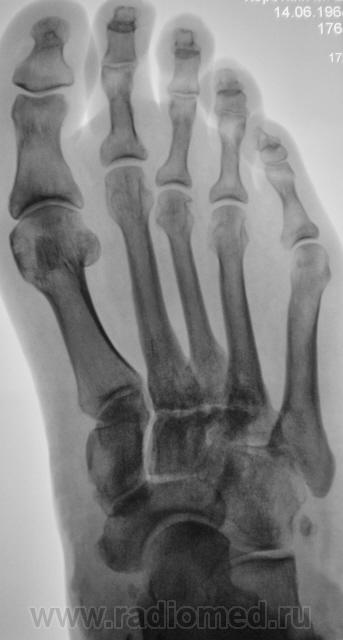

Экзостоз ладьевидной кости?

Да, похоже на 2 остеомы на широких ножках.